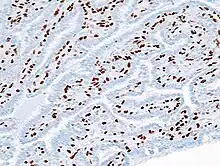

| Histopathology of intraductal papilloma of the breast by excisional biopsy. Immunostaining for p63 protein. | |

Histopathology of intraductal papilloma of the breast by excisional biopsy. Hematoxylin and eosin stain.- Histopathology of intraductal papilloma of the breast by excisional biopsy. Immunostaining for alpha-smooth muscle actin.